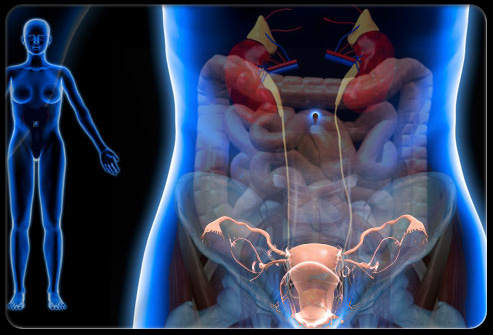

什么是盆腔疼痛?

盆腔疼痛可能因为多种疾病或症状出现。比如,盆腔疼痛可能是单纯的痛经,也可能是阑尾炎或者膀胱问题,这些病症可好可坏,有些完全不是问题,有些则需要急救治疗。对于大多数人来说,如果出现盆腔疼痛的问题则需要去医院有专业人士进行检查。